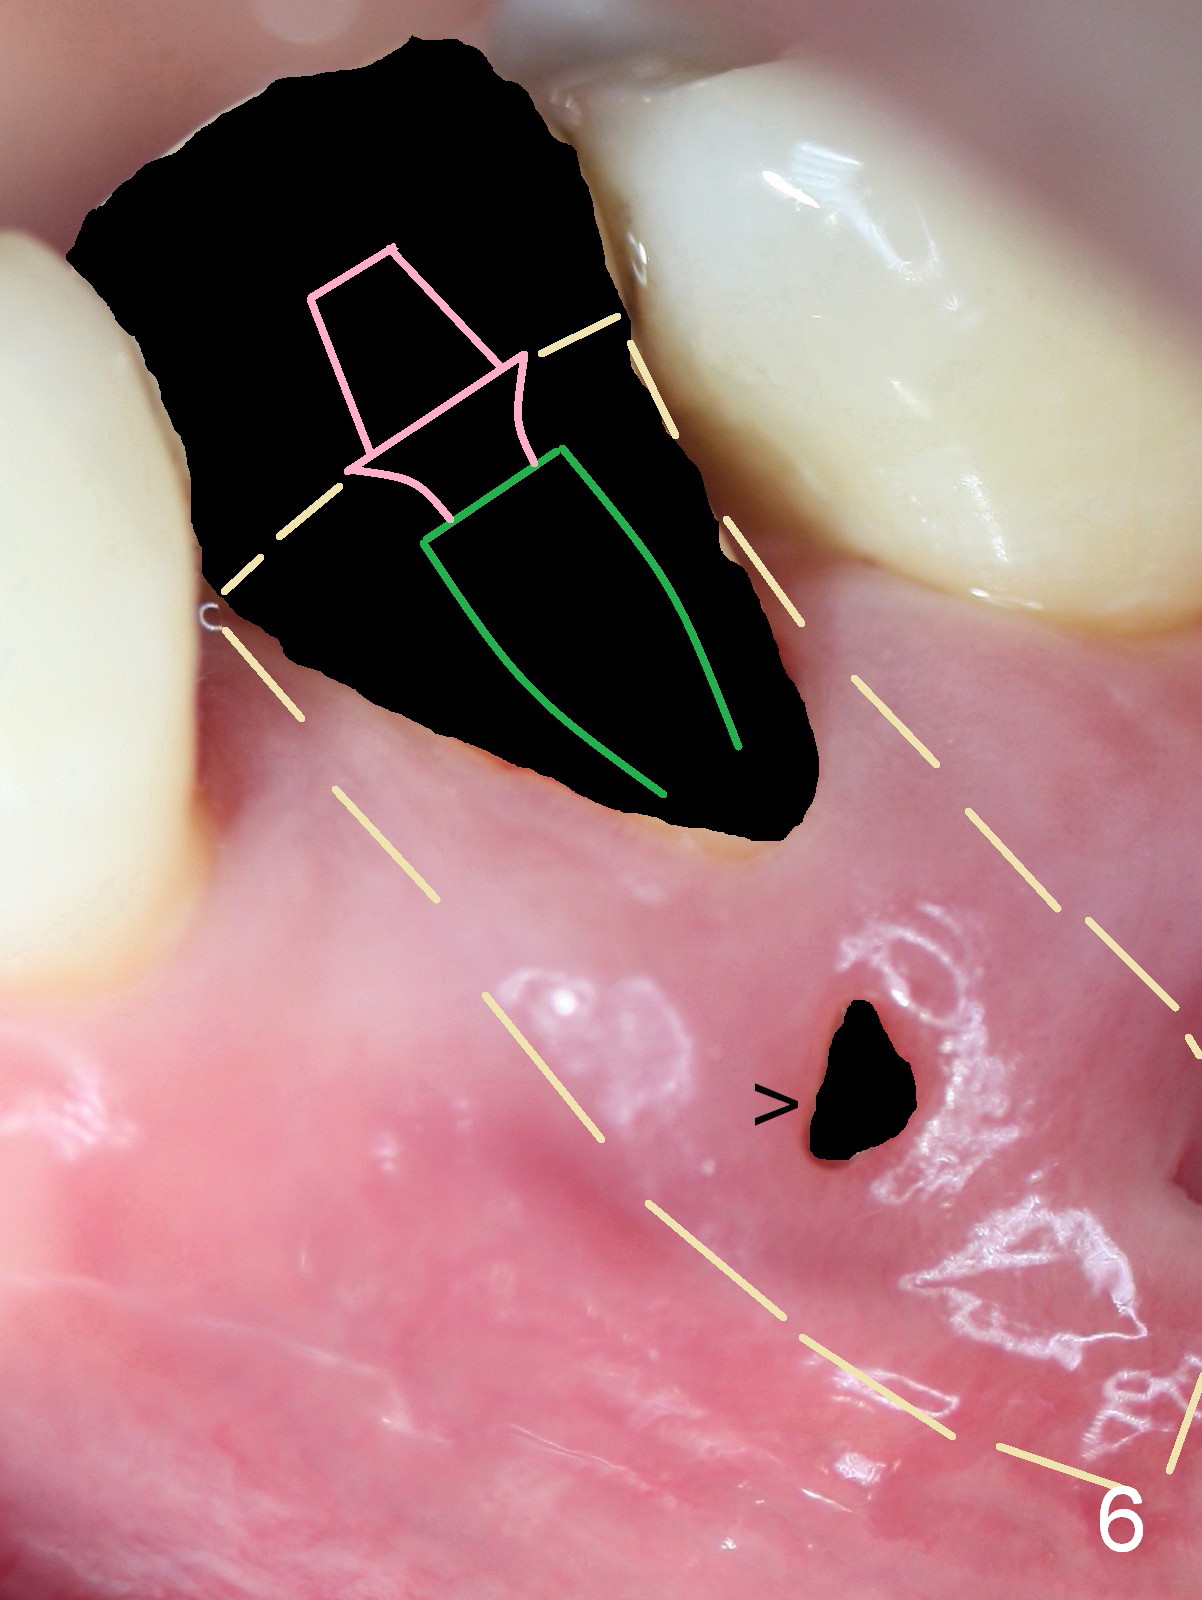

A 45-year-old man (JT) has endo failure at #20 with fenestration (Fig.1,2 black >) and fistula (white <). Insertion of a Gutta Percha at the fistula (Fig. 3 <; PA taken 2 years ago) indicates that the infection is dervied from the apex of the tooth #20. The socket will be soaked with 2% Xylo, 1:50,000 Epinephrine gauze. A 4.5x17 mm tissue-level (Fig.4) or 14 mm bone-level implant is placed as lingual as possible (Fig.5 green). If primary stability is achieved, an abutment is placed (pink). A large piece of resorbable membrane is used to cover the buccal defect (including buccal recession, fenestration and fistula (Fig.6 yellow dashed line). Two small pieces of non-resorbable membrane are placed to cover the gingival recession and the fenestration (Fig.7 white dashed line, buried underneath the edge of the gigniva). Then place bone graft buccally. Place a small piece of gauze (one layer) or plastic (from Tatum implant bag) over the 2nd membrane over the gingival recession and fabricate an immediate provisional. When the acrylic is partially set, remove the gauze or plastic from the provisional. After trimming and polishing, the provisional is cemented to securely keep the 2nd membrane in place. When the wound is healing and the 2nd membrane is stable, trim the buccal extension of the provisional. It is expected that the buccal hard and soft tissue will regenerate over the implant.